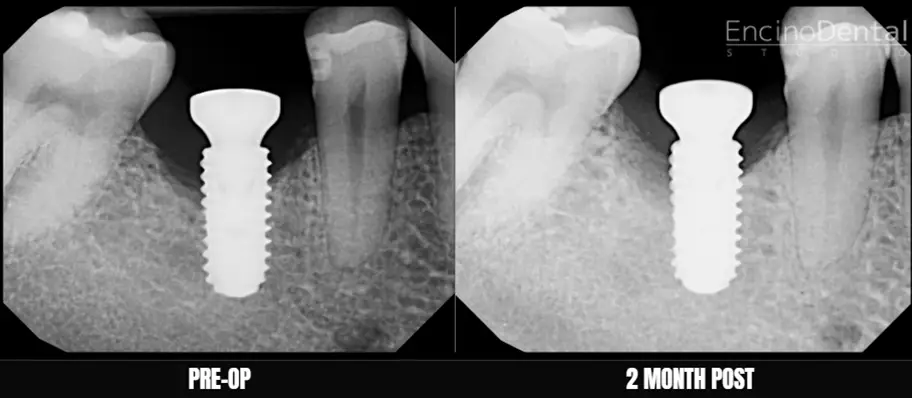

Before and After LAPIP at Encino Dental Studio